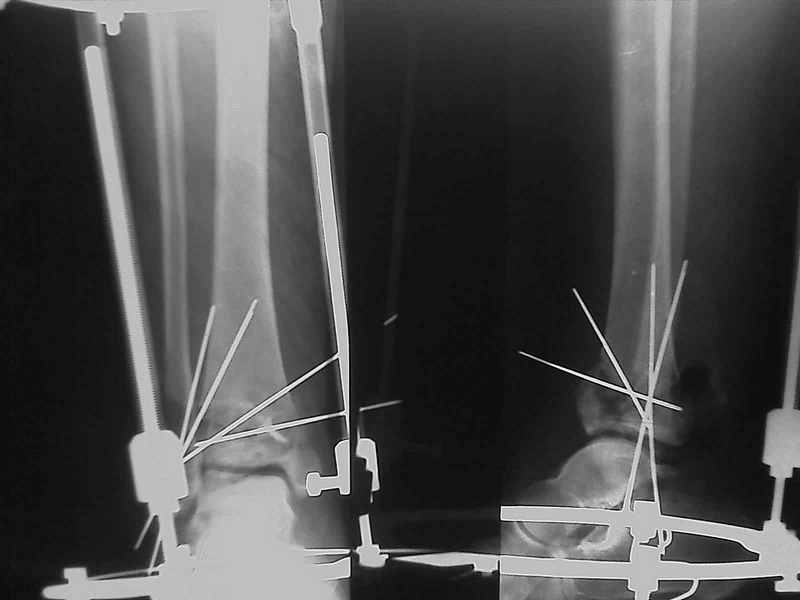

Снова приветствую вас, коллеги. К моменту вступления в обсуждение

аксакалов, операция была,  увы, выполнена(31.10.07.) Начали с доступа к

наружной лодыжке, произвели ее фиксацию спицами, развернули кусок

заднего края, наложили дистрактор,  затем произвели дистракцию, фиксацию

спицами дистального эпиметафиза б/бк,Рентгено-контроль. синтез наружной

лодыжки 1/3пластиной. из двух коротких разрезов сформирован канал под

медиальную тибиальную пластину  LCP. Края ран ушиты без натяжения.

Прочувствовать жесткость фиксации винтами с угловой стабильностью не

удалось, поэтому дистрактор оставлен на энное время.

На представленных R-снимках не окончательный вид после остеосинтеза.

Дистальная опора давила на стопу, пришлось ее  сместить проксимально, в

рез-те чего, она закрыла щель сустава, последние снимки не информативны.